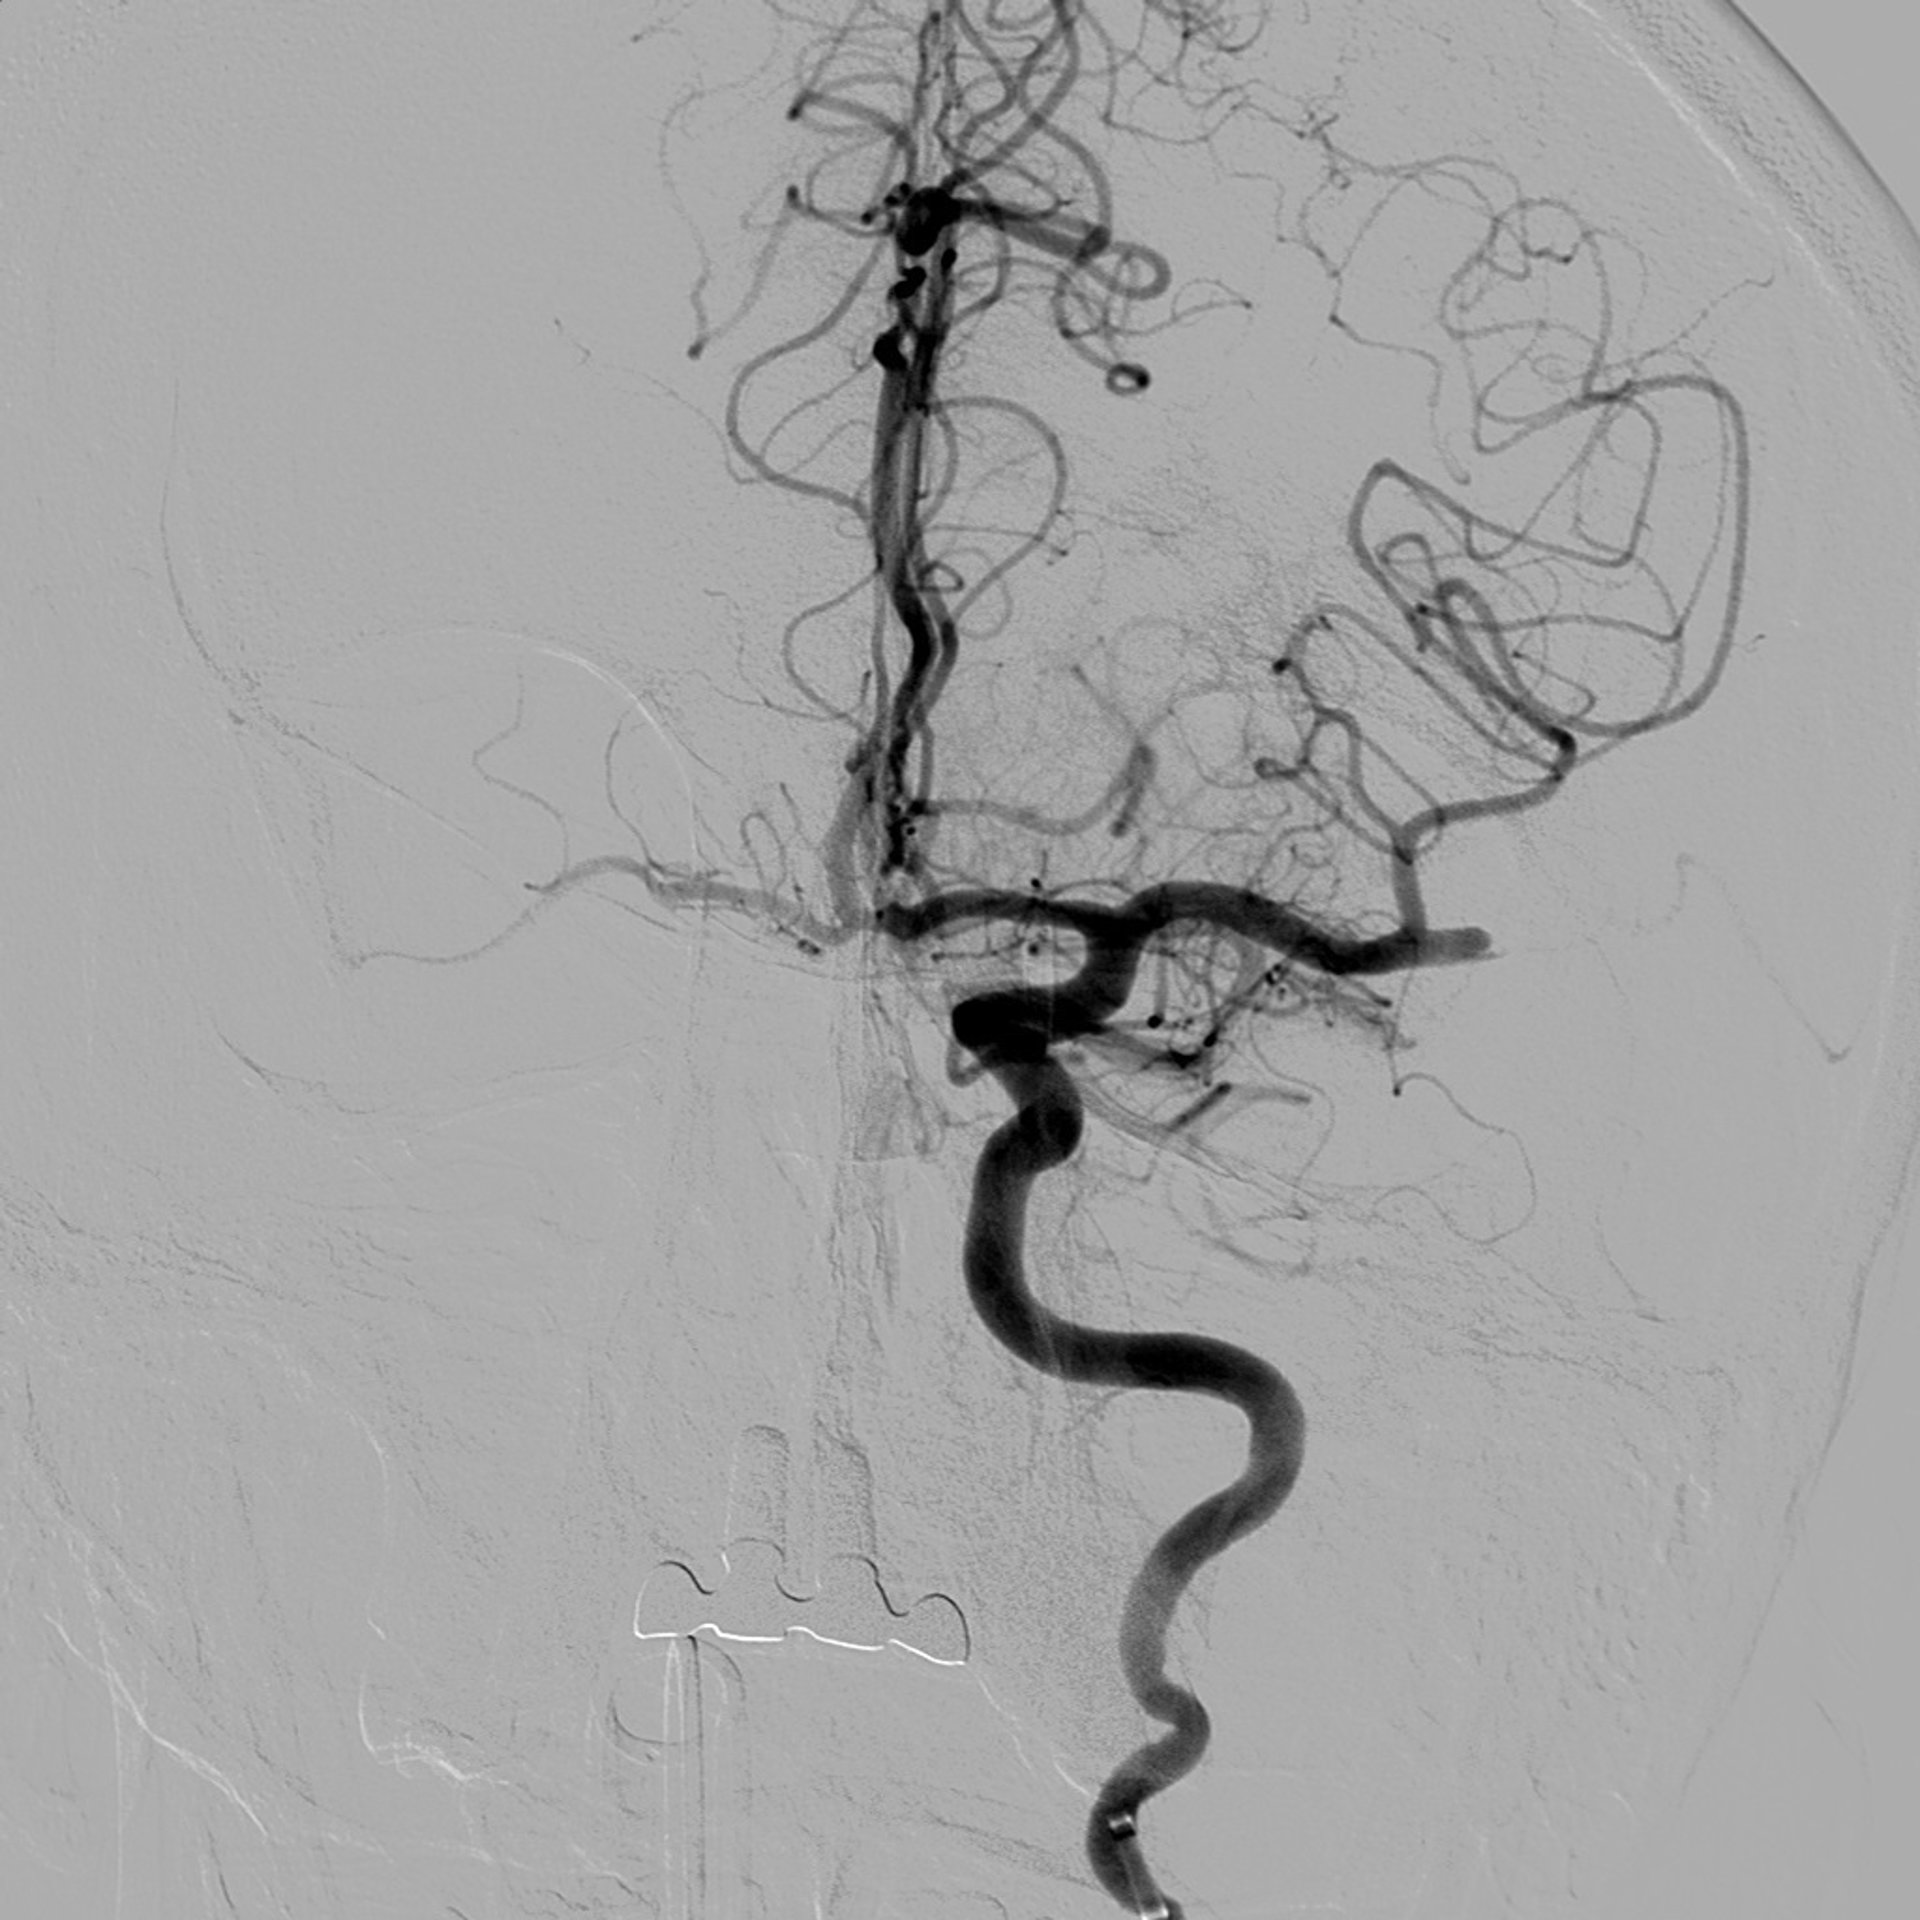

Imagen de arteria obstruida con trombo

Actualmente, la Unidad de Ictus del HUNSC cuenta, además de la cobertura farmacológica terapéutica, con otras técnicas especializadas incorporadas recientemente para el tratamiento de determinados casos con la aplicación en sala de una técnica intervencionista denominada trombectomía mecánica de la que se han beneficiado hasta el momento 85 pacientes diagnosticados de Ictus y con una tasa de éxito de recanalización superior al 80%.

El procedimiento, realizado en la sala de radiología vascular intervencionista se pone en marcha una vez diagnosticada la obstrucción de la arteria intracerebral mediante TAC. Ya en sala se realiza una arteriografía para confirmar los hallazgos y valorar la posibilidad de extraer el trombo o coágulo en el paciente candidato.

Para ello se introduce un catéter a través de la arteria femoral hasta la arteria carótida interna del lado afecto, para posteriormente, y a través de este mismo catéter, introducir otro más fino denominado microcatéter que será el responsable de acceder a la arteria intracerebral que presenta el trombo. Una vez en la zona se coloca un dispositivo que actúa en forma de red (stent-retriever) que permite 'atrapar' y recuperar el coágulo de sangre, para finalizar retirando el stent del mismo modo que se efectúa con los catéteres y así comprobar que la arteria vuelve a ser permeable.